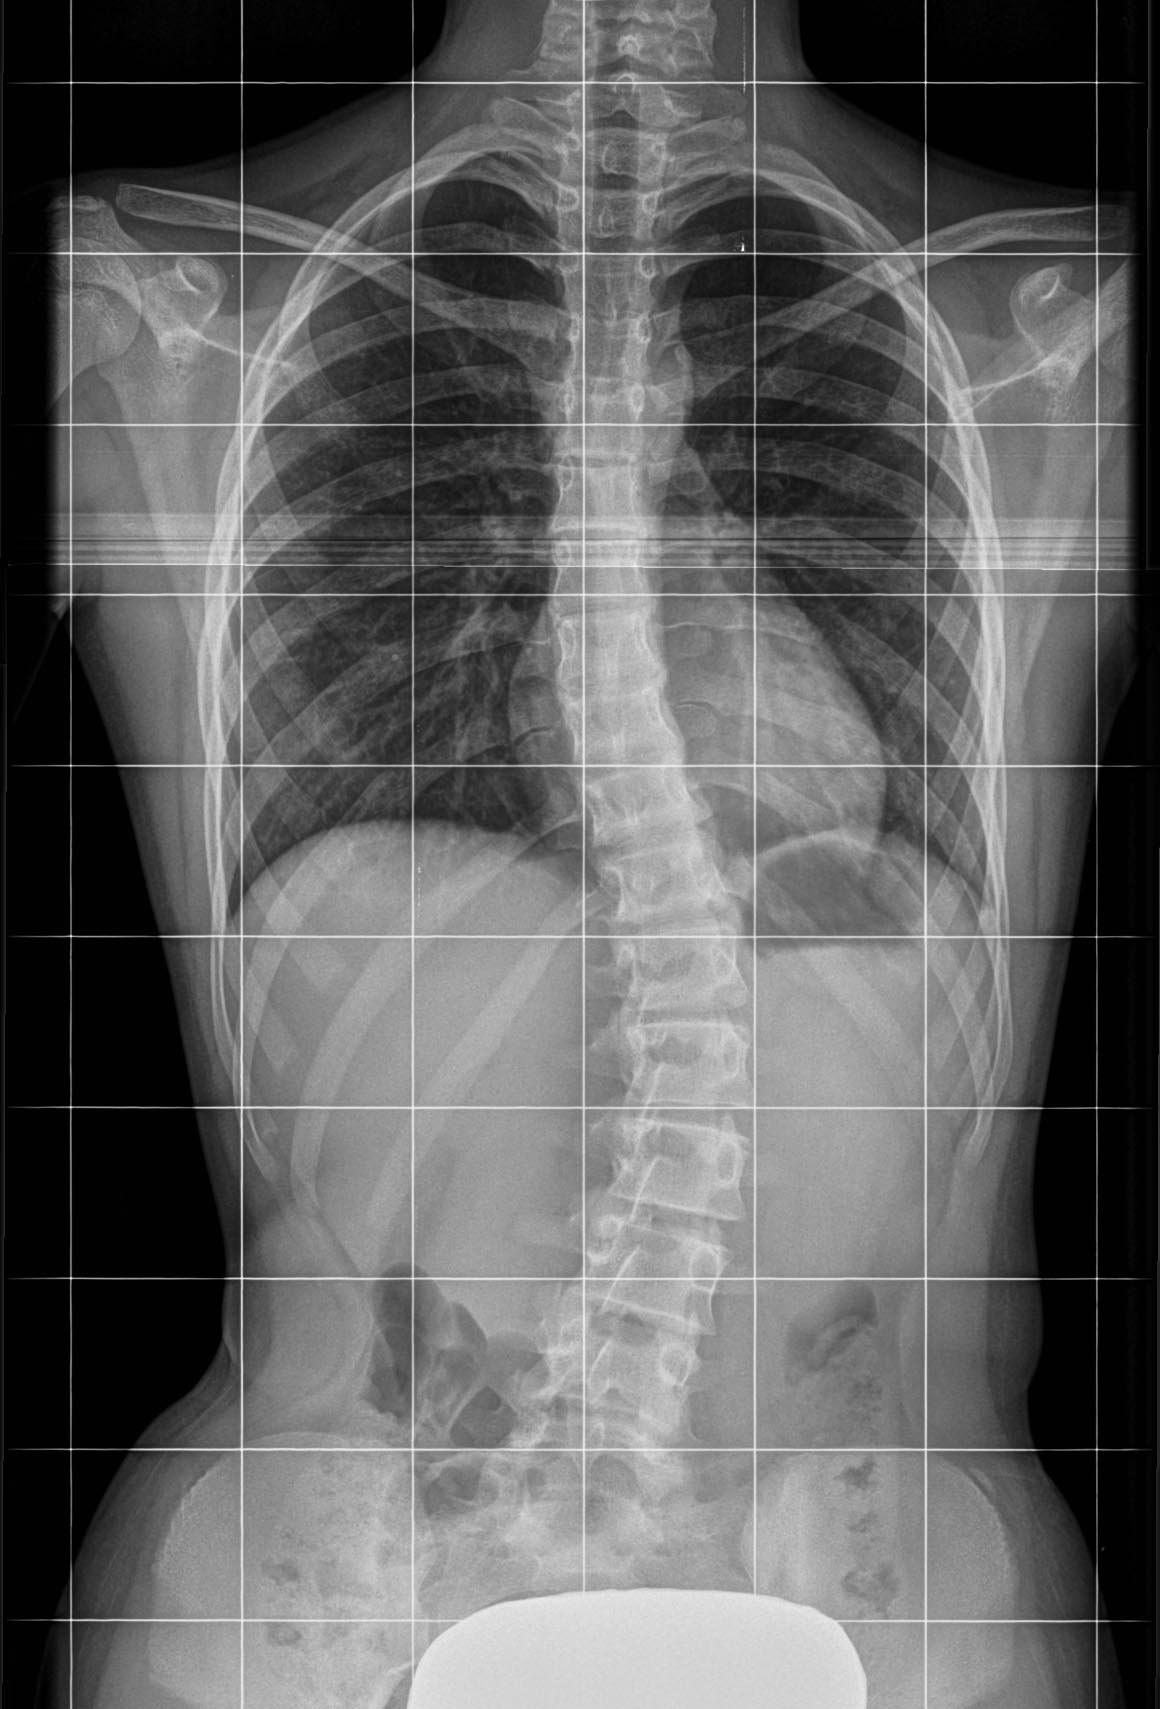

MRI je vrhunska diagnostična metoda. Pokaže strukturo hrbtenice, kostne spremembe, stanje medvretenčnih ploščic, morebitne hernije ali vnetja. Skratka, pokaže vse, kar je vidno v sami zgradbi telesa.